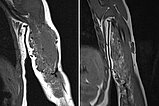

Comparison of coronal T1-weighted MRI sequences from February 2019 (left) with September 2021 (right). In these T1-weighted images, fat is shown as hyperintense (white). In the right image, it is easy to see that the amount of fat in the tumor has increased over time. This is typical of an infantile hemangioma that is partially in involution.